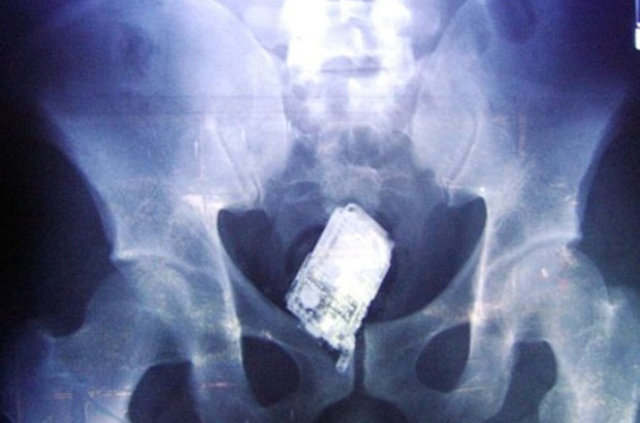

İzmir'deki Tepecik Eğitim ve Araştırma Hastanesi Çocuk Gastroenteroloji Bölümü'nün, yabancı cisim yutan çocukların nefes ve borusu ile midelerinden çıkarttığı, anahtarlık, madeni para, saat pili, ataç, çengelli iğne ve çivi gibi objeler görenleri şaşkına çevirdi.

Çocukların nefes ve borusu ile midelerinden çıkartılan, anahtarlık, madeni para, saat pili, ataç, çengelli iğne ve çivi gibi objeler görenleri şaşkına çevirdi. Anne ve babaların çok dikkatli olması gerektiğini söyleyen Doç. Dr. Maşallah Baran, şöyle dedi:

Genellikle yabancı cisimler 'X' ışınıyla görülebilir. Direk grafi ile metal ve 'X' ışınına duyarlı cisimleri rahatlıkla görebiliyoruz. Ama plastikleri göremiyoruz. Bu durumda oyuncağın bir parçasıyla yutulan parçayı anlamaya çalışıyoruz."

"Madeni paralar çok sık yutulan cisimler arasında, 4-6 haftaya kadar midede ya da bağırsaktaysa bekleyebiliyoruz ancak yemek borusunda olan vakalarda yutulan yabancı cisim ne olursa olsun endoskopi işlemi yapıyoruz. İkili mıknatıs yutmalarına hemen müdahale ediyoruz. Yoksa ciddi zararlara yol açabiliyor.